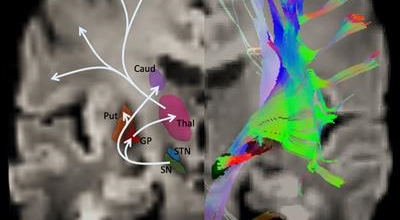

파킨슨병은 도파민 분비 신경 세포의 소실로 발생하는 질환으로 알려져 있는데요 도파민이란 뇌의 신경세포에서 만들어지는 물질로 세포와 세포 간의 신호를 전달하는데 이용되는 신경 전달 물질 중 한가지로 이 도파민이 감소함에 따라 파킨슨병이 걸린다고 하는데 이 도파민 세포가 떨어지는 이유는 아직 정확히 밝혀지지 않았다고 합니다.

파킨슨병 치료에는 수술치료, 약물치료, 초음파 치료 등이 있는데 파킨슨병은 완치가 어려워 조금이라도 개선을 하는 방향으로 가야 합니다. 현재 가장 일반적인 치료는 약물치료로 레보도파라는 도파민을 보충하는 약물로 치료를 하는 경우도 있어요.

약물치료의 경우 며칠 동안 복용하는 것이 아닌 장기적으로 계획하고 복용하여하며, 처음부터 많이 복용하다 보면 약으로 인한 부작용이 나타날 수 있어 주의하여야 합니다. 약물치료 시작 후 3~5년 뒤에 이상 운동증, 운동 요동 현상과 같은 부작용이 나타난다면 수술적 치료를 고려해야 합니다.